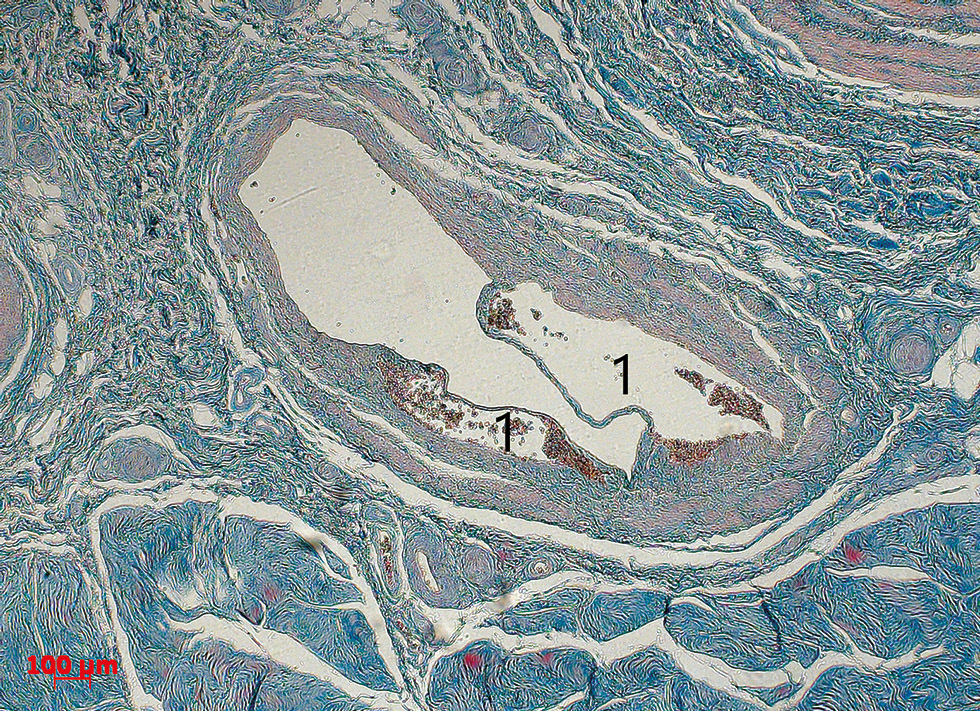

Клапанные паруса или створки представлены двумя подвижными частями, которые и обеспечивают закрытие просвета вены при ретроградном кровотоке. Створки клапана состоят преимущественно из коллагеновых волокон и являются очень тонкими (рис. 3). Это позволяет клапанам, будучи негромоздкими структурами, обеспечивать отток крови в одном направлении. Сторона клапана, обращённая к току крови, покрыта эндотелием, имеющим уплощённую форму. На поверхности, обращённой к синусу, эндотелий более высокий, полигональной формы.

Рис. 3. Клапан глубокой дорсальной вены на поперечном срезе. Определяются клапанные валики (1) и створки (2). Окраска гематоксилин-эозином. Ув. ×100.

Расположенные зеркально на противоположных стенках вены две створки при функционирующем клапане формируют собственно два купола венозного клапана. Просвет венозного сосуда, находящийся между стенкой вены и клапанным парусом, формирует синус (или пазуху) венозного клапана. Именно там задерживается кровь при закрытом венозном клапане (рис. 4). Стенки синуса, таким образом, играют роль буфера, принимающего на себя вместе с самим клапаном энергию движущейся крови. При изменении гемодинамических условий и открытии венозного клапана кровь из синусов продолжает движение к сердцу.

Рис. 4. Клапан глубокой дорсальной вены с частичным перекрытием просвета. В синусе клапана (1) скопления эритроцитов. Окраска по Маллори. Ув. ×50.